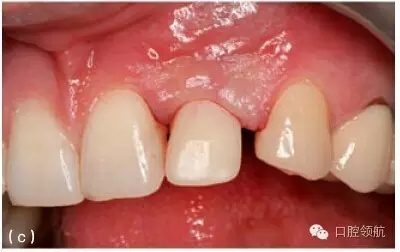

圖9.31 (a)對于深覆患者,當(dāng)種植體植入角度偏頰側(cè)的時候,要相應(yīng)增加植入深度,以避免下頜牙切緣與種植體接觸;增加操作空間,有利于形成逐漸過渡的修復(fù)體穿齦外形。(b)從種植體平臺到修復(fù)體頸部,逐漸過渡的臨時冠軸面外形。(c)臨時冠就位的臨床觀,在美學(xué)區(qū)域,對于非手術(shù)式的組織塑形,推薦2~3個月的塑形時間。